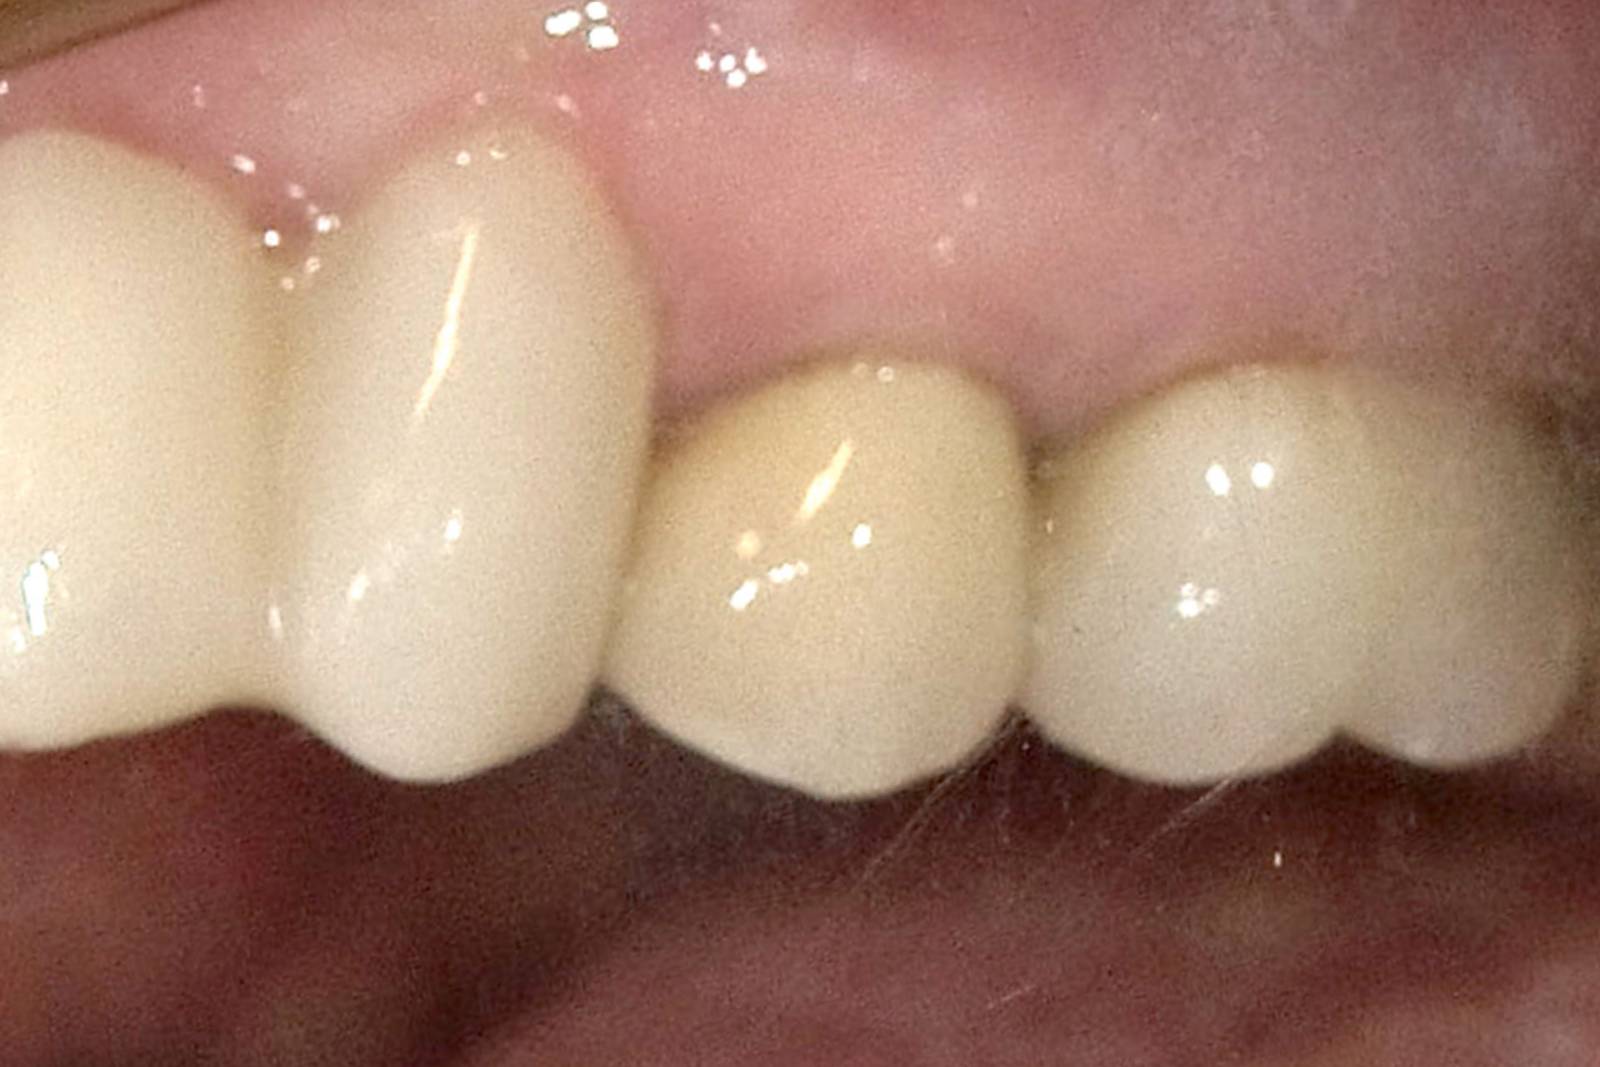

After

Chairside-fabricated restoration made from an advanced lithium disilicate ceramic, CEREC Tessera.